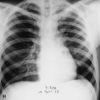

¡ÒÌâä (Plague) ÊÒà˵Øà¹×èͧÁÒ¨Ò¡àª×éÍẤ·ÕàÃÕ ¡ÒÌâäà»ç¹âäµÔ´µèÍ·ÕèÁÕÍѹµÃÒÂÃéÒÂáç·ÕèÊØ´ àÁ×èÍÁÕ¡ÒÃà¡Ô´âä¹Õéµéͧá¨é§¤ÇÒÁµÒÁ¾ÃÐÃÒªºÑ­­ÑµÔ»éͧ¡Ñ¹âäµÔ´µèÍ ¾.È.2523

ÍÒ¡Òâͧâä¡ÒÌâä»Í´ : ÍÒ¡Ò÷ѹ㴠ä¢éÊÙ§ ˹ÒÇÊÑè¹ »Ç´ËÑÇÃØ¹áç ÍÒ¡ÒÃäÍà¡Ô´¢Öé¹ã¹ 24 ªÑèÇâÁ§ àÊÁËе͹ááà˹ÕÂÇãÊáÅéÇ¡ÅÒÂà»ç¹ÊÕʹÔÁËÃ×Íá´§Ê´ ÁÑ¡äÁèÁÕ»×é¹á¼Å㹻ʹ ¶éÒäÁèÃÑ¡ÉÒ : µÒÂÀÒÂã¹ 48 ªÑèÇâÁ§